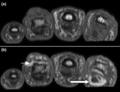

(a) T1-weighted and (b) short tau inversion recovery (STIR) magnetic resonance images of lumbar and lower thoracic spine in psoriatic arthritis. Signs of active inflammation are seen at several levels (arrows). In particular, anterior spondylitis is seen at level L1/L2 and an inflammatory Andersson lesion at the upper vertebral endplate of L3.

Magnetic resonance images of sacroiliac joints. Shown are T1-weighted semi-coronal magnetic resonance images through the sacroiliac joints (a) before and (b) after intravenous contrast injection. Enhancement is seen at the right sacroiliac joint (arrow, left side of the image), indicating active sacroiliitis.